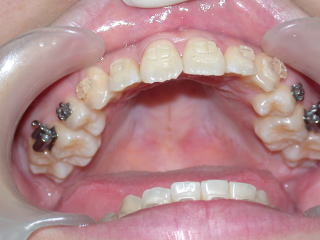

2024年2月20日

2024年5月15日装置除去